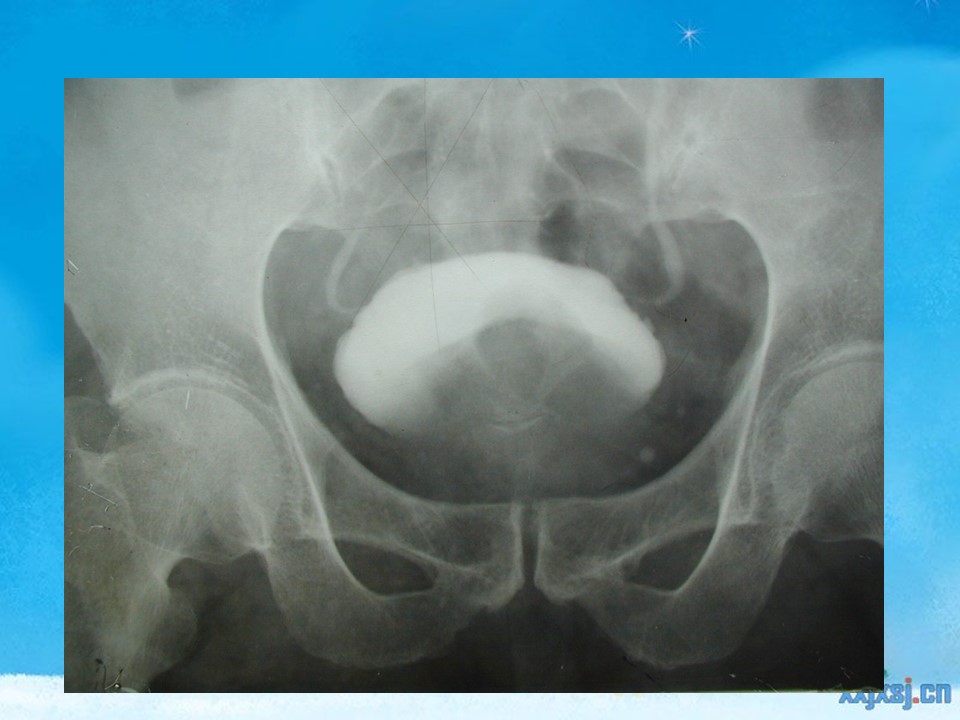

“腹部、盆腔影像诊断学PPT” 的相关文章